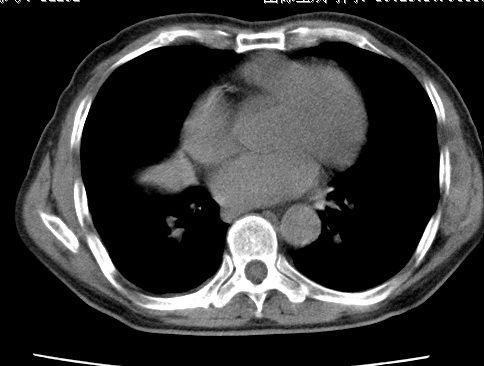

考虑右肺中叶不张,请大家发表意见

右肺中叶不张、肺门轮廓增大,占位不除外;建议增强,必要时支气管镜详查。

右肺中叶支气管闭塞,中叶肺不张,右侧肺门见肿块影。中心型肺癌的可能大。建议支气管镜检查。

右中叶体积明显缩小,且其支气管未显示,先考虑:中心型肺癌班右中叶肺不张。

建议:支气管镜检查。

考虑右肺中叶中央型肺癌并右肺中叶肺不张;建议:行纤支镜检查。

右肺门旁类圆形肿块影,右肺中叶不张,建议纤支镜检查。

1右肺门旁类圆形肿块影,右肺中叶不张,建议纤支镜检查

2右侧胸膜增厚,右侧叶间胸膜区钙化

3右肺下叶小囊状透亮影考虑肺气肿